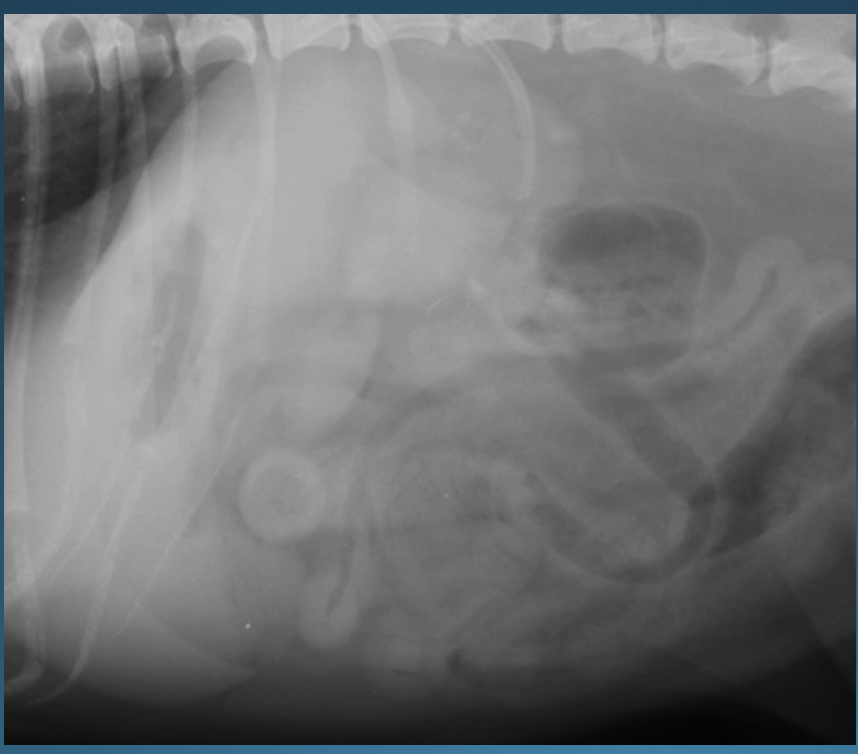

What is shown in this image?

A

normal left lateral view in the dog